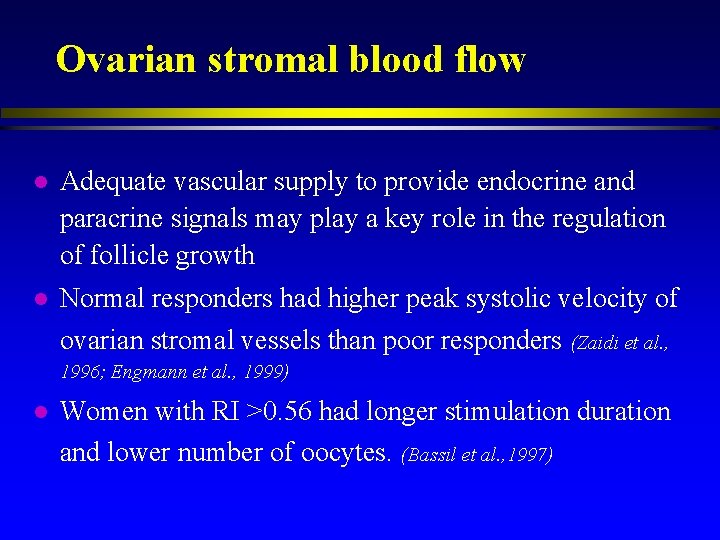

Ovarian stromal blood flow l Adequate vascular supply to provide endocrine and paracrine signals may play a key role in the regulation of follicle growth l Normal responders had higher peak systolic velocity of ovarian stromal vessels than poor responders (Zaidi et al. , 1996; Engmann et al. , 1999) l Women with RI >0. 56 had longer stimulation duration and lower number of oocytes. (Bassil et al. , 1997)